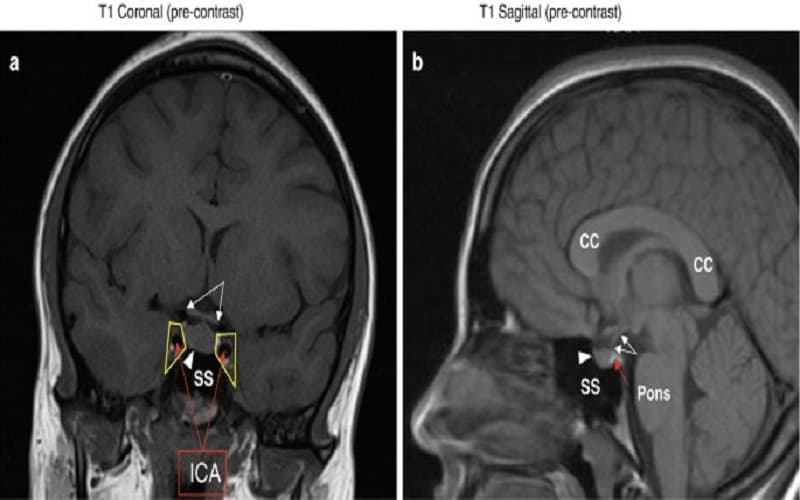

3.3. Chẩn đoán hình ảnh

Chụp cộng hưởng từ (MRI) tuyến yên được coi là tiêu chuẩn vàng trong đánh giá cấu trúc tuyến yên. Phương pháp này giúp phát hiện chính xác các khối u, nang, tình trạng teo hoặc tổn thương tuyến yên đang chèn ép, từ đó gây rối loạn chức năng nội tiết và ảnh hưởng đến quá trình sản xuất hormone của cơ thể.